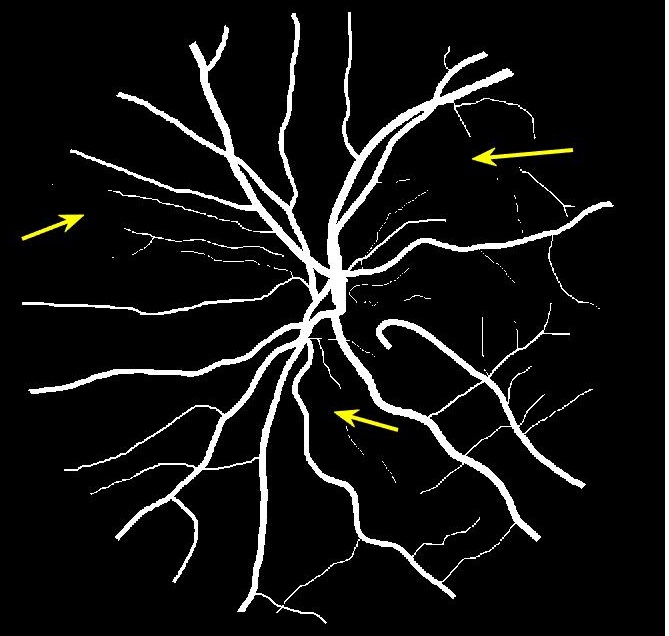

Figure 4 (a) shows an example retinal image followed by its ground truth manual segmentation in Figure 4 (b). Figure 4 (c) shows segmentation result for scaling factor when using the original HR images to train the U-Net followed by the results when trained on the super resolved images generated by , (Figure 4 (d)), (Figure 4 (e)), (Figure 4 (f)), SR-RF (Figure 4 (g)), SSR (Figure 4 (h)) and (Figure 4 (i)). Obviously the results from provide results most similar to those of HR images. This is also validated by the quantitative results in Table 3. The areas where different methods are unable to obtain accurate segmentation are highlighted by yellow arrows. Due to poor quality of super resolved images most of the methods do not segment the finer vasculature structures, while SSR and SR-RF are unable to segment some of the major arteries. Importantly, our method performs much better than the low resolution image () which performs poorly due to low resolution.